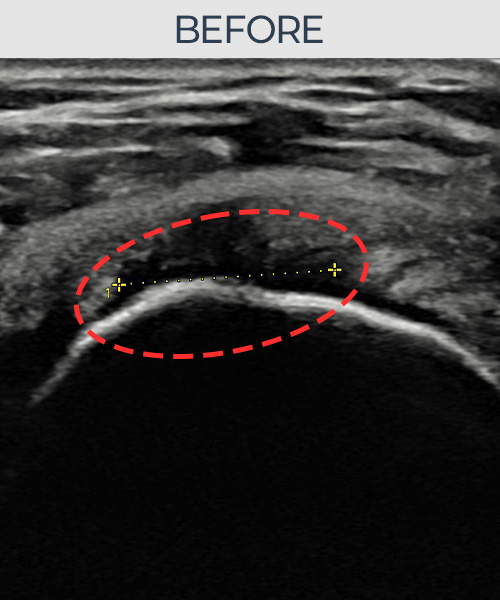

비수술 치료 전후사진

비수술로도 파열된 인대를

물리적으로 재건해 드립니다

인대강화주사만으로는 해결되지 않던 인대파열.

플래티넘정형외과에서는 수술없이도 물리적으로

파열된 인대를 재건

하는것이 가능합니다.